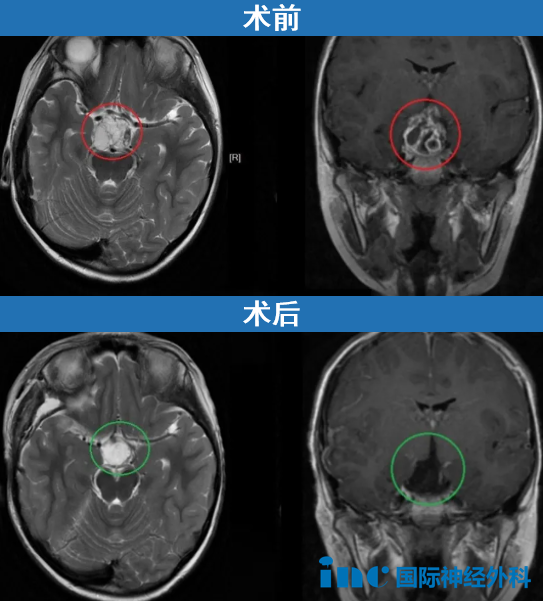

3岁的小豪因为玩耍时不慎摔倒而起了个大包,父母带着孩子去医院检查以防万一,却查出了一个不小的脑干胶质瘤。辗转各大医院,均认为手术风险太大,术后可能偏瘫。然而,巴教授在咨询时表示:目前脑干肿瘤尺寸已经很大,需要尽快进行手术,预后是良好的。

一直持续生长的肿瘤还会继续压迫脑干,小豪的父母在听到巴教授可以安全切除时毫不犹豫就选择了手术:尽早安全切除,小豪也就能越早摆脱脑瘤。

而事实上他们也不止一次庆幸当初的决定,因为术中巴教授再次发现,短时间内小豪的胶质瘤又增大了,这也证实了术前的猜想——脑干胶质瘤从未停止生长。

幸好,手术十分顺利,小豪的胶质瘤被安全切除。从咨询巴教授到决定手术,他们仅仅用了1天,在此之后,一直害怕、心疼的他们心里的石头终于落地,这台成功的手术也收获了较好的结果。